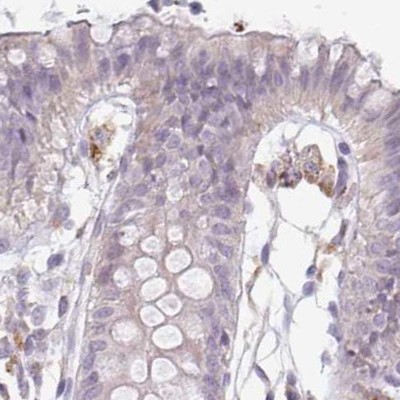

Immunohistochemical staining of human colon, fallopian tube, liver and testis using Anti-TMEM237 antibody HPA052596 (A) shows similar protein distribution across tissues to independent antibody HPA054732 (B).